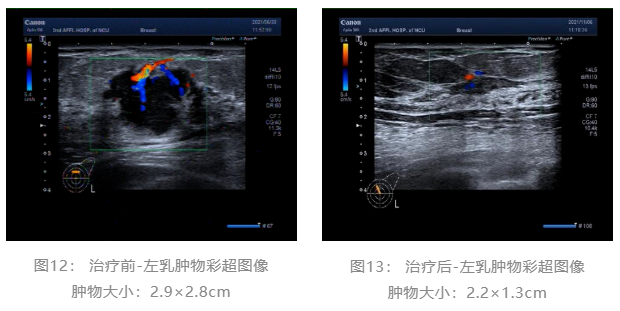

▌治疗前后影像学对比:

乳腺彩超:

术前评估:新辅助治疗期间患者无明显不适,一般状况可。新辅助治疗后左乳房肿瘤及腋下肿大淋巴结退缩明显,疗效评估PR,未发生不良事件,择期可行左乳癌改良根治术。

随着靶向药物的研究进展,越来越多的的研究开始探索在不影响患者预后的前提下,是否可以避免使用蒽环类化疗药物。KRISTINE研究8结果证明,TCbHP方案在新辅助治疗中的有效性和安全性;Ⅱ期TRYPHAENA研究9结果也提示,在曲妥珠单抗联合帕妥珠单抗双靶治疗的前提下,使用以紫杉和卡铂为基础化疗的pCR结果与紫杉和蒽环为基础的化疗相当;TRAIN-2研究10对比了FEC-TCbHP和TCbHP方案在HER2阳性早期乳腺癌中的疗效,结果显示两组的疗效终点没有显著性差异,两组pCR分别为67%和68%,但是使用蒽环类化疗的患者出现了更高比例的发热性中性粒细胞减少(10% vs 1%)和心脏毒性事件(8.6% vs 3.2%)。目前对于HER2阳性乳腺癌的新辅助治疗,2022.V2版NCCN指南11也不再将含蒽环类方案作为首选的推荐。在此病例中,患者选择了THP方案进行新辅助治疗,在治疗6个周期后,影像学评估为PR,术后病理提示患者达到了pCR,再次证实该方案的有效性。